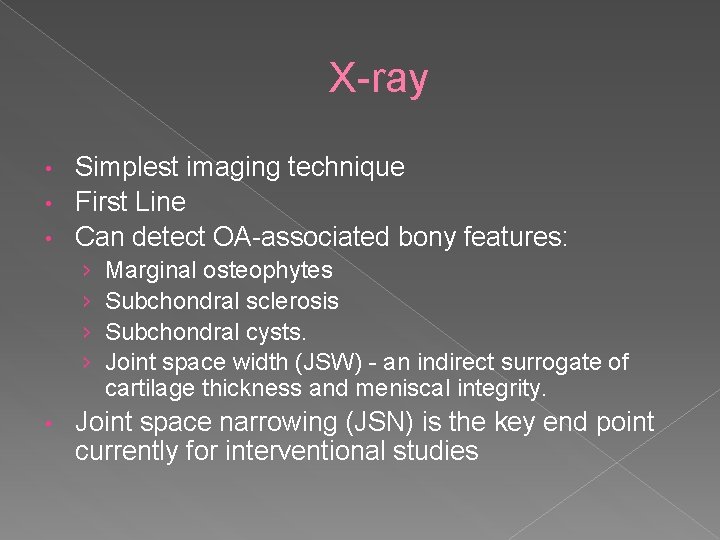

X-ray Simplest imaging technique • First Line • Can detect OA-associated bony features: • › › • Marginal osteophytes Subchondral sclerosis Subchondral cysts. Joint space width (JSW) - an indirect surrogate of cartilage thickness and meniscal integrity. Joint space narrowing (JSN) is the key end point currently for interventional studies

X-ray Findings • • • Non-uniform narrowing of joint space Subchondral bony sclerosis Marginal osteophyte formation Subchondral Cyst formation Gross deformity in advanced cases

Joint Space Narrowing